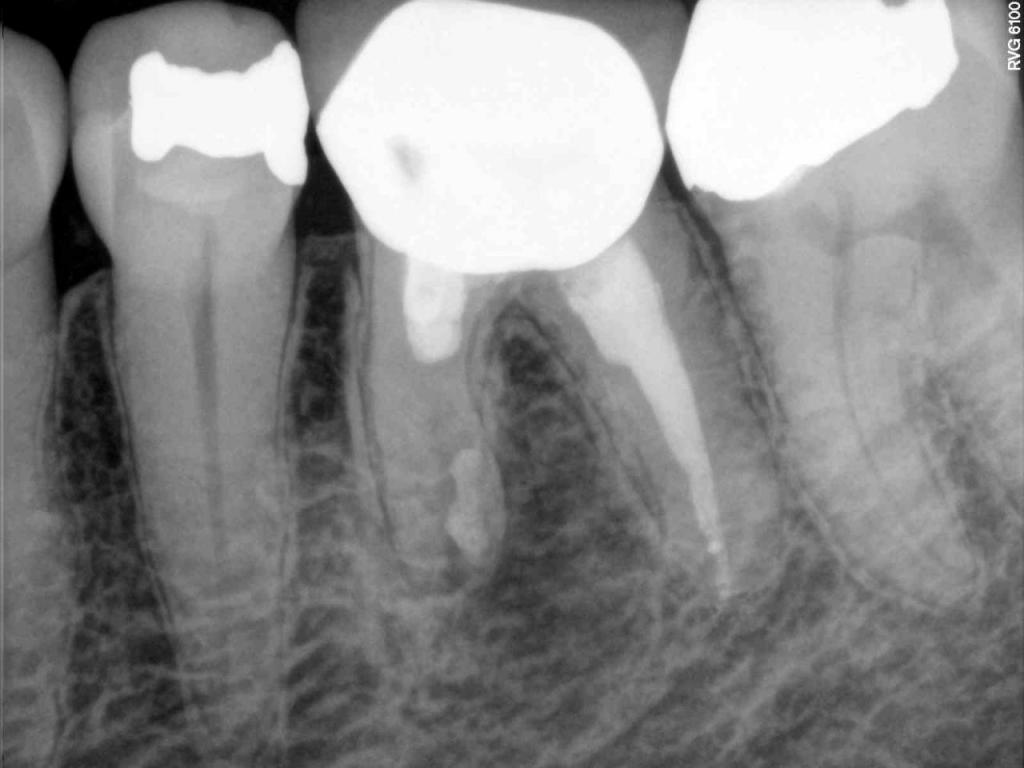

Although the primary use of visual documentation is for patient charts, dental images provide a meaningful way to communicate with patients about their care needs. Digital imagery is a vital tool for educating patients and an essential way to share information with office staff, colleagues and referring doctors. Digital technology has allowed Southcenter Endodontics to enhance our practice and improve the delivery of care to our patients. Below you will see images of “Before” and “After” scenarios. By clicking on a thumbnail image below, you will be able to see and a larger view of the x-ray taken at Southcenter Endodontics and notations made regarding each film.